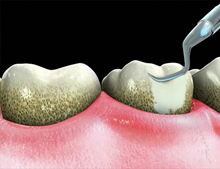

Scaling is one of the most important procedures of treatment of periodontal disease. Scaling involves the use of manual tools that remove hard tartar deposits on the tooth surface.

Tartar is considered a local irritation factor, and because of this must be removed periodically.